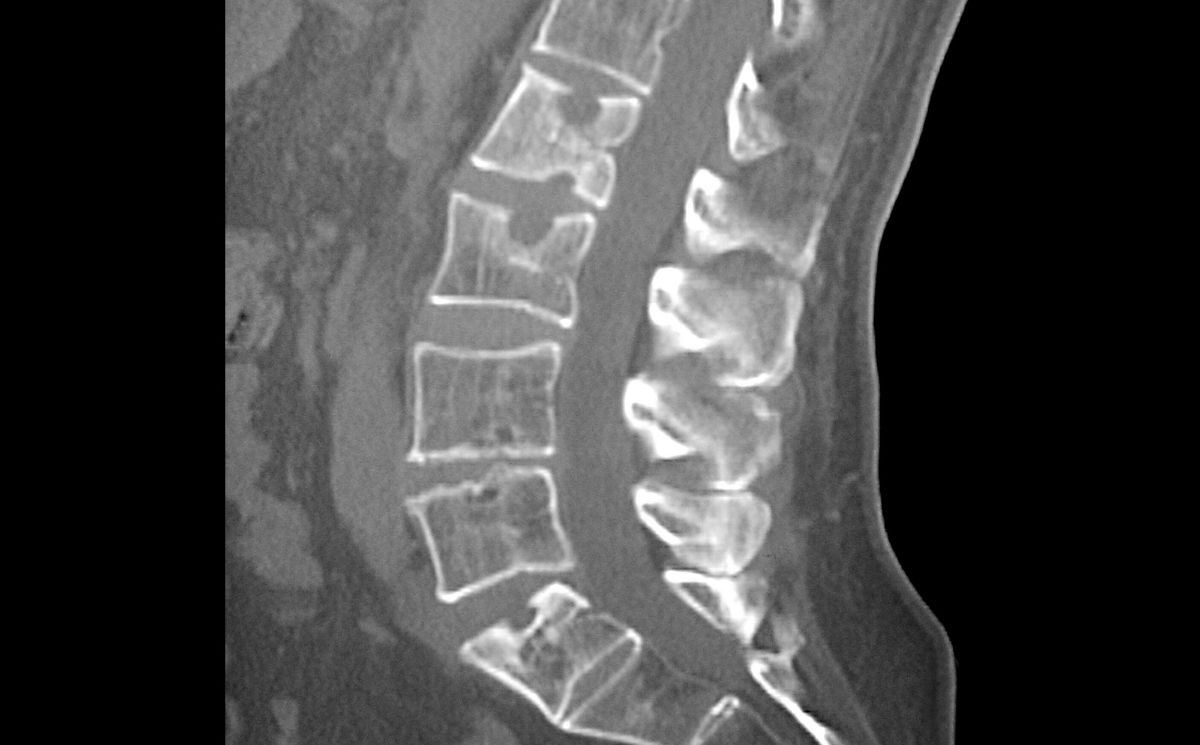

Is My Back Pain Arthritis . Problems with the discs that cushion the spine and. back arthritis is not one disease; many forms of arthritis and related conditions can cause back pain, stiffness and swelling. the main symptom of lumbar arthritis is lower back pain. Rather, many different types of arthritis may cause back pain and. If it lasts much longer, doctors consider it chronic back pain, and arthritis may. Back pain (especially neck pain and lower back pain). About 80% of back pain lasts less than a week. Back pain is a leading cause. Stiffness or feeling less flexible. The lower back is the most common site of arthritis back pain. About 80% of back pain is acute and usually lasts one to seven days. Back pain is one of the most common reasons people seek medical help or miss work. the most common spinal arthritis symptoms include: Otherwise, it’s considered chronic and may be caused by arthritis.